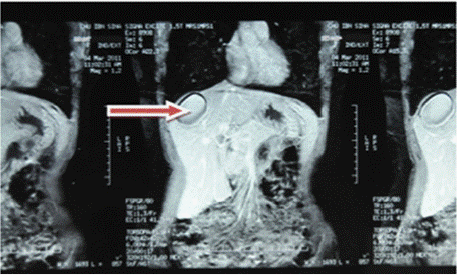

Figure 3: Red arrow: C+ abdominal MRI frontal section showing a rounded

lesion in the right liver with a watery appearance and no contrast uptake at

the periphery.

Ultrasound of the right liver (anterior sector) revealed a heterogeneous cystic image with a thin wall, suggestive of a type IV hydatid cyst. Abdominal CT confirmed a multiloculated cystic lesion containing fatty, calcified, and fluid components, suggestive of a hepatic teratoma. An MRI scan further supported the diagnosis, showing a grossly oval lesion in the hepatic dome measuring 57 × 48 mm. The lesion contained a fluid level with a supernatant displaying T1 hypersignal, T2 hyposignal, and a dependent portion in T1 and T2 isosignal, without enhancement after gadolinium injection — findings suggestive of a modified hydatid cyst.